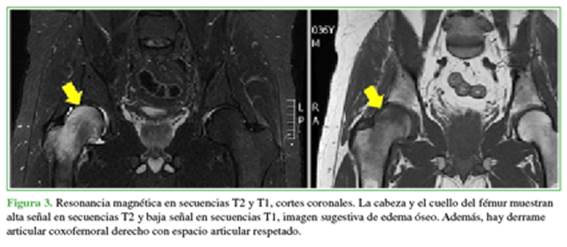

En la resonancia magnética, se puede observar que la cabeza y el cuello del fémur derecho muestran alta señal en secuencias T2 y baja señal en secuencias T1 tanto en los cortes axiales (Figura 2) como en los coronales (Figura 3). Además, se puede detectar el derrame articular en secuencias T2. La señal de la cadera izquierda es normal.